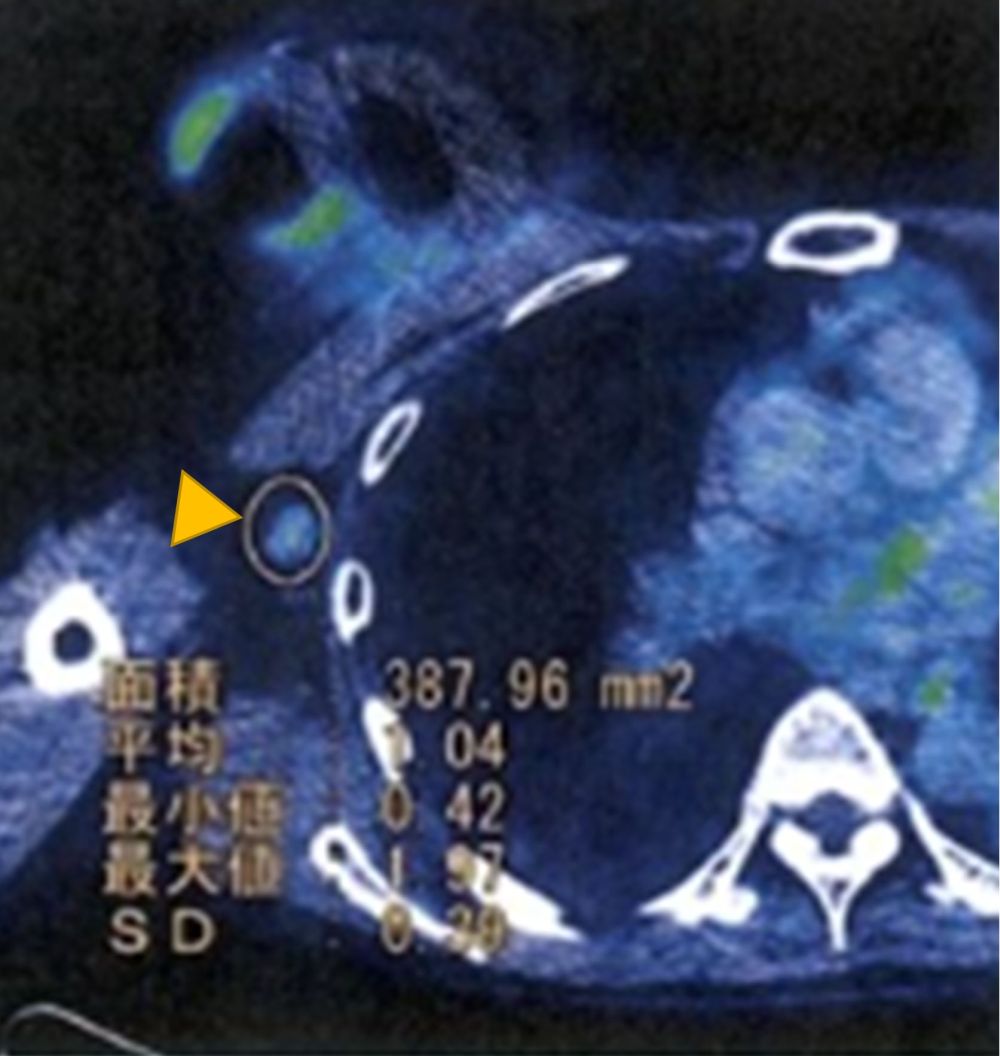

A 56-year-old Japanese transgender individual identifying as a woman had bilateral textured SBI inserted 25 years previously by a cosmetic surgeon for feminizing breast augmentation. She had undergone male to female sex reassignment surgery 12 years before the current presentation. She had taken hormonal drugs for about 5 years in her thirties. She took no oral medications such as anticoagulants or hormonal drugs after age 40. Two years prior to her visit to our department, her right breast became swollen without any specific cause. Redness and pain were observed 2 months prior to her visit. We observed redness, swelling, and abnormal morphology of the right breast (Figure 1). Blood tests showed no elevated inflammatory response or tumor marker or coagulation system abnormality (WBC 5,030/µl, CRP 0.11 mg/dL, PT-INR 0.9, APTT 30.6 seconds, IL-2 657). Computed tomography (CT) image showed a mass had formed under the ruptured SBI, and positron emission tomography (PET/CT) image showed swelling of the right axillary lymph node (Figures 2 and 3). Ultrasound-guided aspiration of fluid was performed and cytologically examined. However, flow cytometry showed no significant findings with few lymphocytes, and Giemsa banding could not be performed with little cell counts. Mammotome biopsy suggested a diagnosis of hematoma, but the possibility of breast implant–associated anaplastic large cell lymphoma (BIA-ALCL) could not be ruled out. The SBI ruptured just before surgery, so the mass and the axillary lymph node were surgically removed (Figure 4). Pathologic examination of the excised specimen revealed only hematoma formation and inflammatory granulation. At follow-up at 6 months postoperatively, there was no reformation of hematoma (Figure 5).

Figure 3. PET-CT findings. Yellow arrow indicates swelling of the right axillary lymph node.